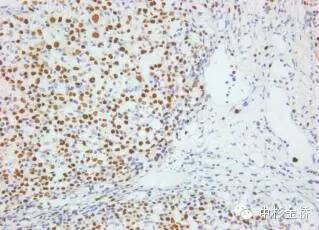

圖為EBER原位雜交染色DBA顯色,蘇木素復(fù)染

EBER是EB病毒編碼的小RNA,在EB病毒感染的細(xì)胞核中高拷貝存在。根據(jù)EBER的序列設(shè)計(jì)的EBER RNA探針,可以用于石蠟切片,具有較高的特異性和靈敏度,該試劑盒廣泛應(yīng)用于美國、歐盟等各國。